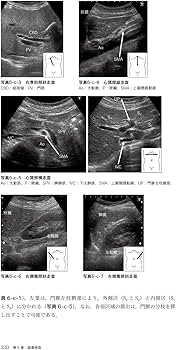

・生理機能検査学・医動物学 第2版・情報科学・医療安全管理学・一般検査学・臨床化学検査学 第2版・微生物学/臨床微生物学 第3版・検査総合管理学 第2版・検査機器総論新品・生理学・病理学/病理検査学・免疫検査学新品・公衆衛生学 2022年度版新品・関係法規ばら売り可能書き込みは写真に写っているもののみあります。マーカーなどがよく引かれている形です。| カテゴリー: | 本・雑誌・漫画>>>本>>>語学・辞書・学習参考書 |